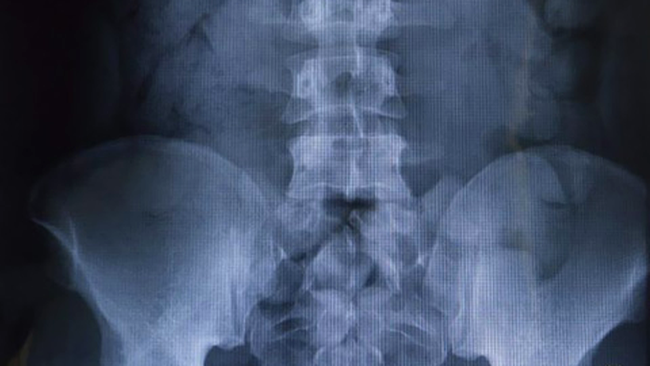

Politistii de frontiera din Geneva au fost uimiti sa descopere una dintre cele mai bizare radiografii, apartinand unui hot care inghitise 123 de prezervative pline droguri.

Radiografia nigerianului care a inghitit

123 de prezervative pline cu cocaina